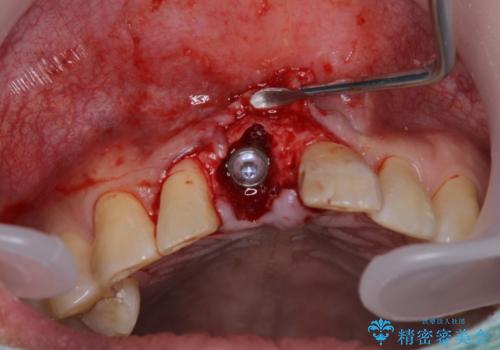

補綴治療としては、インプラントあるいはブリッジの2つがありますが、患者様と相談した結果、インプラントによる補綴治療を選択することとなりました。

咬合力が非常に強いため、インプラントにも過度な力の負担が発生する恐れがあります。

長期間安定して使用いただくために、睡眠時のマウスピースの装着による咬合力の分散が必要となります。

- 外科手術のため、術後に痛みや腫れ、違和感を伴います